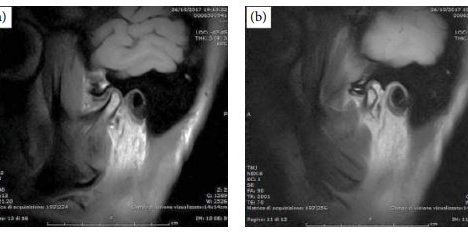

Nel trattamento chirurgico dell’artrosi dell’ATM, l’interposizione di membrana amniotica umana nello spazio intra-articolare risultante da un intervento di artroplastica rappresenta una soluzione promettente. Infatti, tre mesi dopo l’intervento, il paziente ha riferito l’assenza di dolore, una maggiore capacità masticatoria e un miglioramento del range di apertura della bocca.

Tecniche di imaging che cercano di valutare i cambiamenti intra-articolari associati all’uso della membrana umana sono anche raccomandate per una migliore comprensione del corso dei disturbi degenerativi nei pazienti sottoposti a questo trattamento.